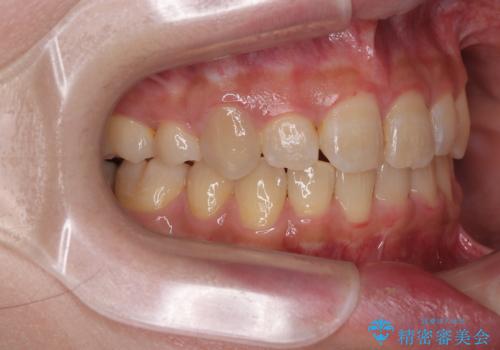

- 上下の八重歯を気にして来院された患者様です。

非抜歯矯正で歯列を整えると、治療後に口元が今よりも突出する可能性が高かったため、上下左右の小臼歯4本を抜歯し、ワイヤー装置にて矯正治療を行うこととしました。

右上の八重歯の影響で、右側は上顎歯列が前方位の咬み合わせとなってしまっていたため、上顎は第一小臼歯を、下顎は第二小臼歯を抜歯することで咬み合わせや上下正中を調整することとしました。

第二小臼歯抜歯の治療となったため、やや時間はかかりましたが、概ね予想通りの期間で治療を終えることができました。